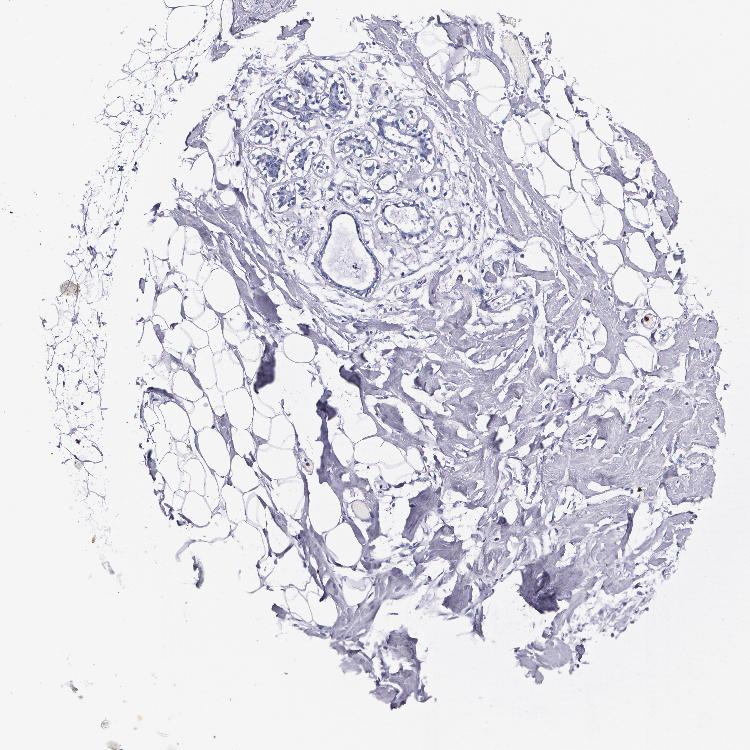

BREAST - Antibody stainingi

Antibody staining in the annotated cell types in the current human tissue is reported as not detected, low, medium, or high, based on conventional immunohistochemistry profiling in selected tissues. This score is based on the combination of the staining intensity and fraction of stained cells.

Each image is clickable and will lead to virtual microscopy that enables deeper exploration of all samples and also displays staining intensity scores, fraction scores and subcellular localization as well as patient and tissue information for each sample.

Antibody HPA024372Antibody CAB002791

Adipocytes Not detectedNot detected

Glandular cells Not detectedNot detected

Myoepithelial cells Not detectedNot detected